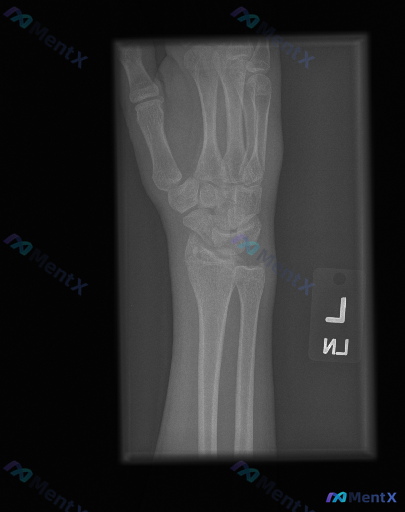

整理到一张左手腕及前臂正位X光片及配套的影像学观察内容,先把客观表现列出来,大家一起读片讨论: 影像客观表现 - 骨骼:桡骨远端可见骨质断裂线,涉及关节面,骨折端有移位和粉碎表现,骨皮质连续性中断,断端有台阶样改变;尺骨茎突也可见骨质断裂线,呈撕脱性表现;舟骨、月骨等腕骨形态大致正常;桡尺骨干皮质连...